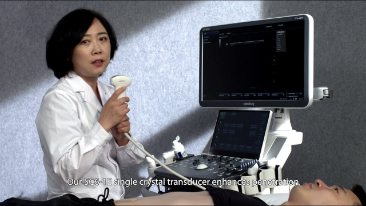

Fin dalla sua fondazione Mindray esplora continuamente nuovi modi per migliorare l'affidabilit├Ā diagnostica. Equipaggiata con la pi├╣ rivoluzionaria tecnologia ZONE Sonography?, la nuova piattaforma ZST+ di Resona 7 porta la qualit├Ā dell'immagine ecografica ad un livello superiore con l'acquisizione per zone e l'elaborazione dei dati canale.

Oltre alla qualit├Ā delle immagini di livello eccellente, Resona 7 migliora anche le capacit├Ā di ricerca clinica il rivoluzionario V Flow per la valutazione emodinamica vascolare, e l'acquisizione piani pi├╣ intelligente dal set di dati 3D per la diagnosi del sistema nervoso centrale fetale. Combinando il pi├╣ intuitivo funzionamento multi-touch basato su gesti e tutte le caratteristiche cliniche essenziali, Resona 7 sta veramente portando nuove tendenze nellŌĆÖinnovazione dellŌĆÖecografia.